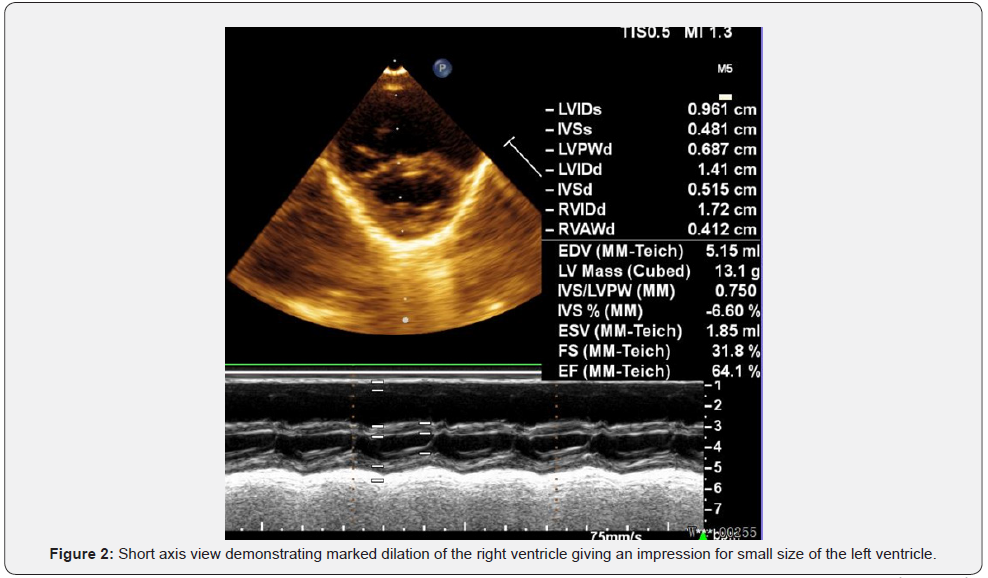

What was noticed on the postoperative echo was that the atrial septal defect type ostium secundum was quite large (Figure 1), with significant left-to right shunting and with marked right ventricular dilation (Figure 2). The left ventricle was hypertrophic, with reversed E/A ratio of the flow through the mitral valve. The left ventricle appeared small in relation to the markedly dilated right ventricle, but the left ventricular size was normal for the weight and the height of the patient.